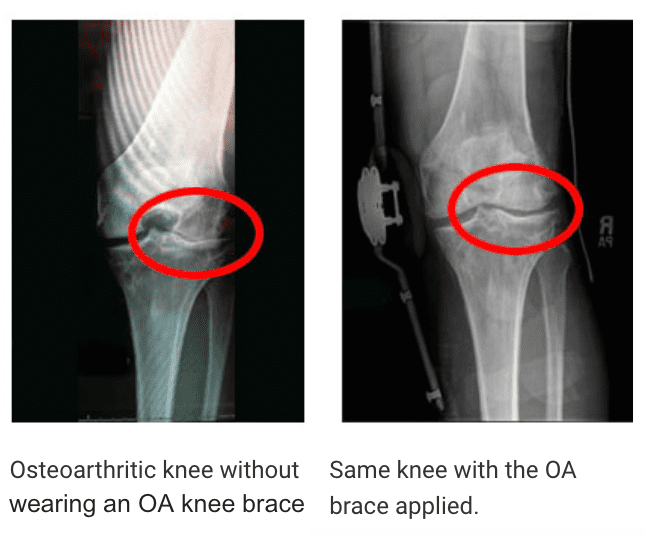

Unloader knee brace reduce pressure on the knees Unloader Knee Brace For Skiing if you’re looking for a way to protect your knees while skiing, a knee brace is a good option. Unloads up to 40lbs from your knee. find out which supports are the best knee braces for skiing and snowboarding, so you can hit the slopes. Shown to significantly reduce knee pain in our patient studies. unloader knee. Unloader Knee Brace For Skiing.